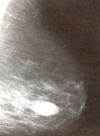

Mammogram of fibroadenoma